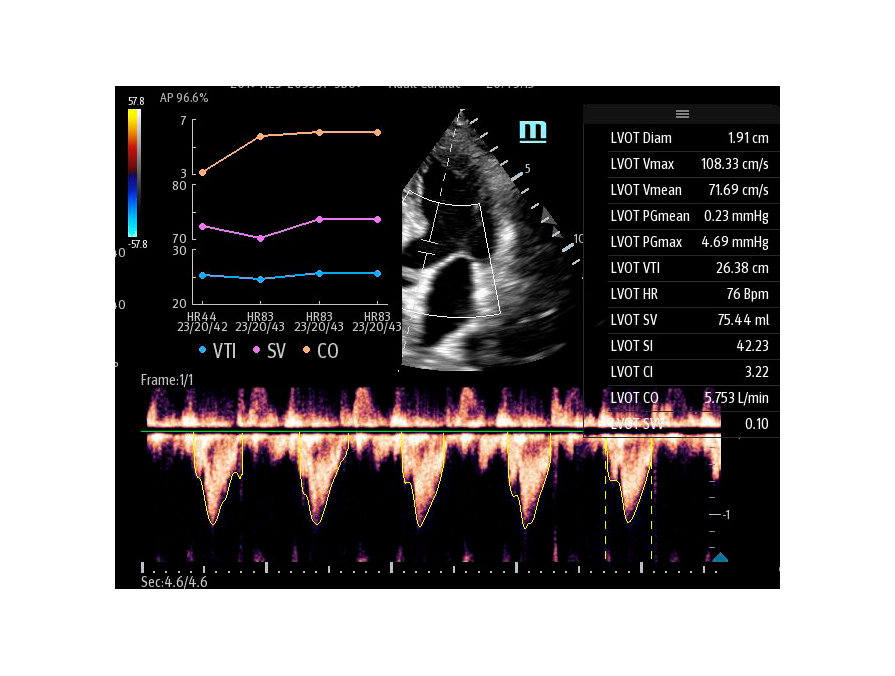

Чтобы использовать уравнение, нужно получить поток выносящего тракта левого желудочка в PW допплере — это достаточно кропотливая работа. В ультразвуковых системах Mindray Resona i9 эта задача решается автоматической оценкой потока выносящего тракта – Smart VTI.

Доктору остается получить 5-ти камерное сечение сердца и нажать одну кнопку на сенсорном экране. Прибор сам выберет расположение контрольного объема, получит спектрограмму и обведет спектр с расчётом всех показателей. Быстро и эффективно.